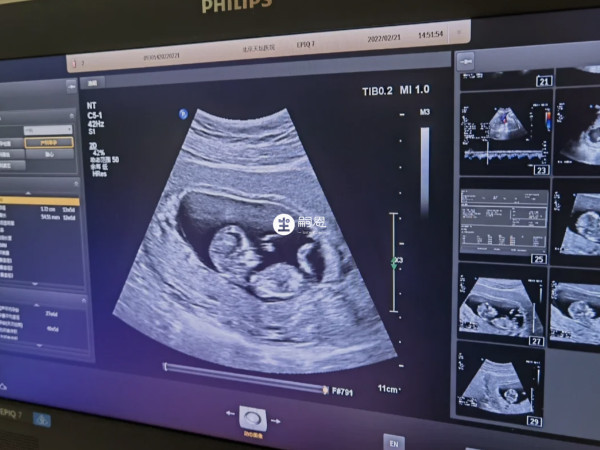

目前,nt檢查結果預測男女的方法在媽媽圈非常流行,許多已生男寶的姐妹分享了自己的nt結果。根據這些孕媽的分享,總結出了預測男孩的特徵,如nt單子上胎兒兩腿之間的白色亮點、尾骨上翹、nt值大於1.5mm等。胎兒的性別一直以來就是人們津津樂道的一個話題,由於國家禁止非醫學需要的胎兒性別鑑定,因此大多數寶媽都會通過民間的一些方法或者是孕期症狀檢查報告單等來進行預測。其中nt單子看男女的方法是非常多人都已經嘗試過的,並且據說準確率可高達90%。

如果nt單子上胎兒兩腿之間有白色的亮點,那就是男孩子的睪丸,所以出現白點的nt單子大概率就是男寶寶。但是如果看到胎兒兩腿之間是三條白線的話,其實就是女孩子陰脣的形狀,懷女寶寶的概率會更大一些。並且有已經生育男寶寶的姐妹驗證,nt單子上確實有白色亮點存在。

身邊不少寶媽都說通過nt檢查報告單中胎兒的姿勢是可以預測胎兒性別的。認為nt單子上如果寶寶的尾骨翹的比較高的,脊柱線和生殖器官之間的夾角大於30度,胎兒整個就是彎曲著身體的形態,這種情況下懷男孩的機率比較大。反之,如果檢查結果上胎兒的尾骨平平的,那麼懷的就是女孩。

如果說檢查結果單子上面的nt值大於1.5的話生男孩,nt值小於1的話生女孩。簡單的來說就是,在nt值正常範圍內,也就是3mm以內,如果nt值偏高一些的話生男孩的機率更大,反之如果偏低一些的話生女孩的機率更大。

孕期NT檢查可以檢測胎兒頸部的透明帶厚度和鼻骨是否正常,從而評估胎兒是否有患唐氏綜合徵等染色體異常的風險。同時,有些人認為通過NT檢查的圖片可以預測胎兒的性別。特此對於NT圖看男女進行了相關整理,有需要的可以瞭解一下。